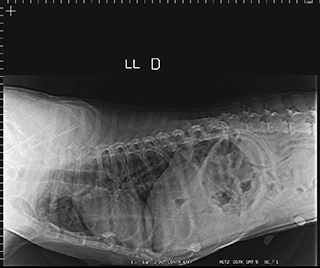

Radiologia Digital Direta / Digital Radiography

As radiografias geradas digitalmente podem ser transmitidas para iPad Apple®, notebooks e smartphones.

iPad com tela Retina Apple® possibilita a visualização das imagens com maior qualidade diagnóstica.

O treinamento aborda a geração das radiografias, a edição digital das imagens, e também a

escolha adequada de técnicas radiográficas como kilovoltagem, corrente elétrica e tempo de exposição.